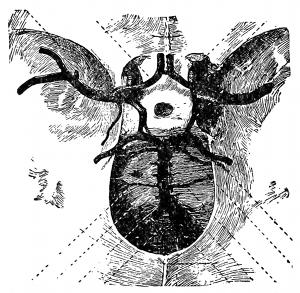

Fig. 1—A, A vertical section of the cuticle; B, the lateral view of the

cells; C, the flat side of scales like (d) magnified

250 diameters.